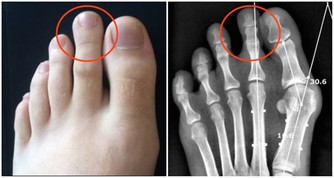

4.低頭族

從不停歇的刷手機不光會讓拇指受累,也會讓頸部產生巨大負擔。

美國《國際外科技術》雜誌刊登的新研究發現,經常駝背、低頭玩手機會容易造成脊椎損傷。因為當頭部彎曲60度時,頸椎承受的壓力會達約45斤重,相當於一個7歲兒童的體重!